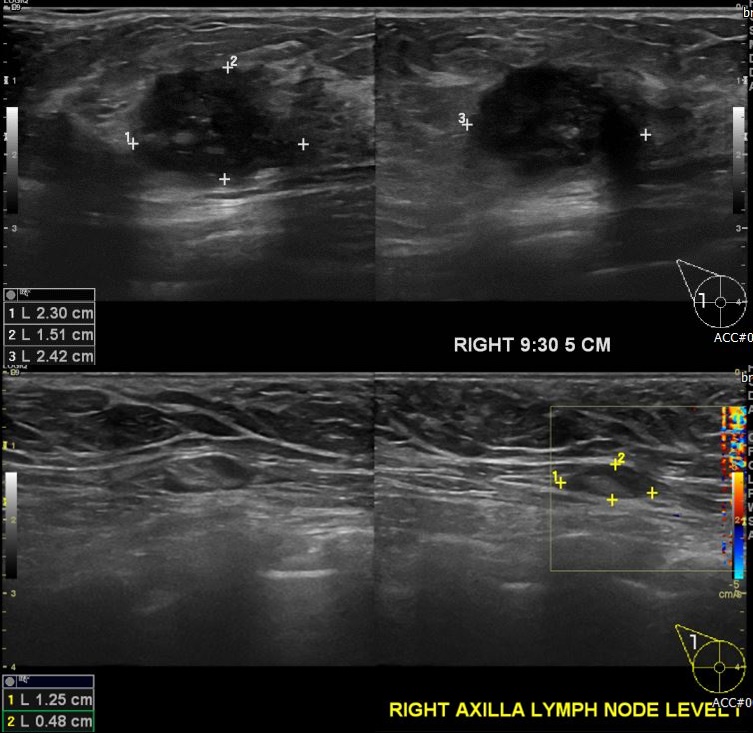

상기환자 우측 유방에 만져지는 멍우리로 내원하신 50대 여성분으로  우측 유방

9:30분 방향에서 5cm 떨어진 거리의 혹 조직검사 시행하여 우측 침윤성 유관암 진단

되었으며, 우측 겨드랑이 림프절 비대부위 세침검사 시행하여 전이암으로 진단 되었습니다.